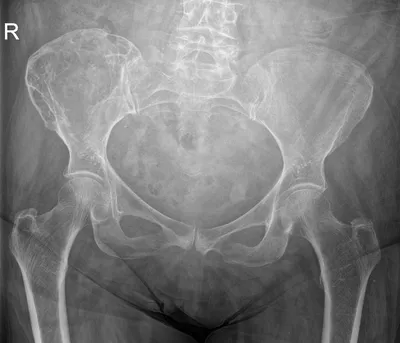

Multiple epiphyseal dysplasia

XRAYPelvisDysplasia+1

4/23/2026